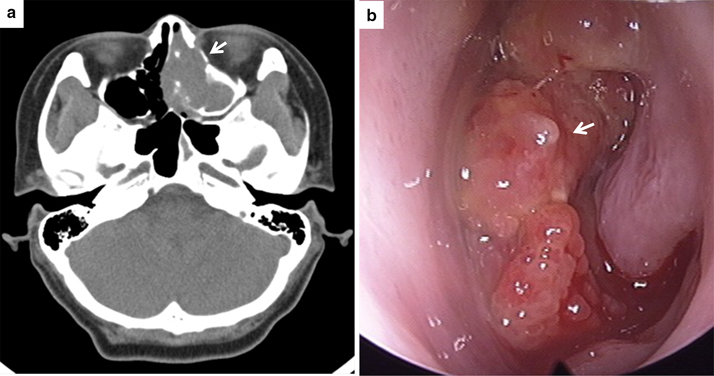

A 42-year-old woman presented with left nasal obstruction and rhinorrhea that had persisted for 6 months. She had already undergone polypectomy of the left nasal cavity under the diagnosis of oncocytic papilloma 3 years prior at another hospital. Based on a follow-up radiologic examination, it was apparent that the mass extent had increased over the previous 3 months. Computed tomography images revealed a heterogeneously attenuating nasal mass involving the middle and inferior turbinate of left nasal cavity, the medial and lateral walls of the left maxillary sinus, and the left ethmoidal sinus. The mass was closely abutting on the nasal septum, causing septal deviation (Fig. 1). A papillary mass with pus was noted in the left ethmoid sinus, maxillary sinus, and septum on nasal endoscopy. The bulging mass on the nasal septum led to right deviation of the septal bone and cartilage. A punch biopsy was performed and the nasal cavity mass was determined to be an oncocytic papilloma based on its papillary growth, bland morphology, slightly oncocytic cytoplasm, lacking a dense or granular appearance, round-to-oval uniform and vesicular nuclei, multilayered epithelium, focal intraepithelial microabscesses, and neutrophils (Fig. 2a, b). Subsequently, nasal endoscopic resection and septal resection with reconstruction were performed.

Fig. 1

a Computed tomography showing a left nasal mass (arrow) involving the middle and inferior turbinate of the left nasal cavity as well as the medial wall of the left maxillary sinus, the lateral wall of the left maxillary sinus, and the left ethmoidal sinus and causing septal deviation. b A bulging mass (arrow) on the nasal septum was noted on nasal endoscopy